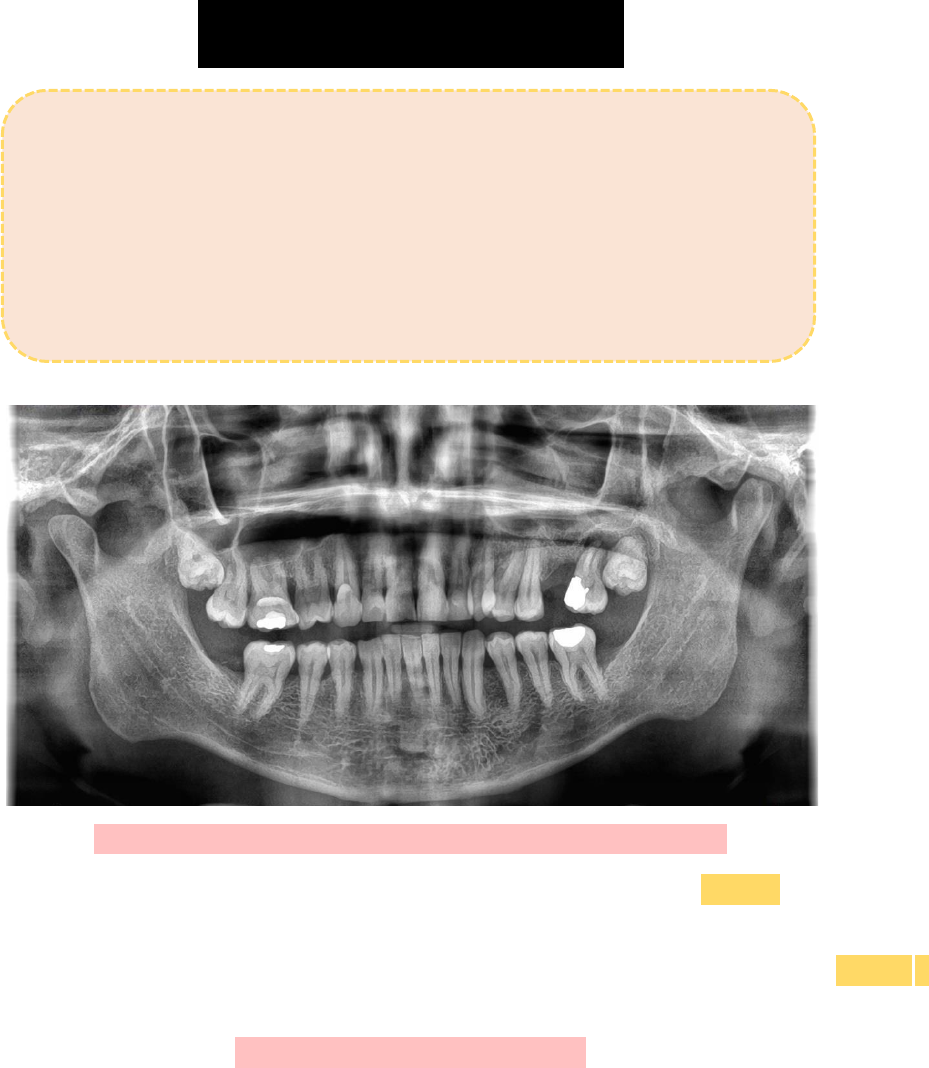

Paciente L.C.P.S, 46 anos, sexo masculino, normossistêmico, compareceu a

clínica odontológica relatando incômodo no último dente superior do lado

esquerdo. Ao realizar o exame clínico da área em questão, constatou-se

que o elemento dentário se encontrava parcialmente erupcionado, sem

mais alterações. No exame radiográfico (panorâmica) foi possível

observar o elemento dentário 28 impactado e o 27 com perda óssea

vertical na região mesial, bem como presença de lesão periapical.

CLASSIFICAÇÃO DA IMPACÇÃO DO DENTE 28:

→ Segundo a classificação de Winter, o elemento dentário 28 encontra-se vertical, em relação a

angulação do longo eixo do 2° molar.

→ Com base na classificação de Pell & Gregory, o elemento dentário 28 encontra-se em uma posição B,

pois a porção mais alta dele está entre o plano oclusal e a linha cervical do 2° molar.